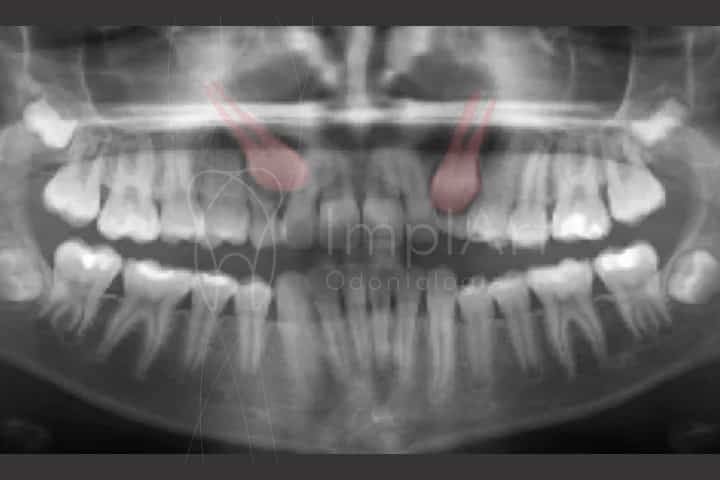

Os dentes impactados são aqueles que não conseguiram atingir a cavidade bucal por falta de força de irrupção ou por não romperem a camada fibrosa.

Também conhecido como dente encravado ou incluso, eles também podem ter estágios intermediários como semi impactados ou semi inclusos, em que eles não estão parados no osso, mas também não tiveram forças para nascer.

Normalmente esse problema ocorre por causa da falta de espaço na arcada dentária, que pode acontecer devido à perda prematura dos dentes de leite ou por deficiência de crescimento ósseo. Os terceiros molares, inferiores e superiores, e os caninos superiores são os dentes que mais sofrem com essa situação.

A imperfeição pode afetar a saúde bucal do paciente quando diagnosticada tardiamente. A mordida pode ficar desalinhada por causa do dente impactado e ele também pode empurrar os outros dentes. Outro possível problema é a reabsorção da raiz do dente que está mais próximo a ele.

Uma vez que o dentista identifica a condição do paciente, o início do tratamento deve ser rápido e eficaz para evitar que outros dentes sejam afetados. Quando não é possível salvar o dente impactado, o primeiro passo é removê-lo. Quanto antes a cirurgia for feita melhor, para evitar que novas complicações afetem o procedimento.

Em seguida, o espaço que seria ocupado por esse dente pode receber um implante dentário. Ele vai realizar as mesmas atividades que o dente impactado teria que fazer. Em todos os casos, o especialista vai determinar qual a melhor conduta e o cronograma do tratamento dos dentes impactados.